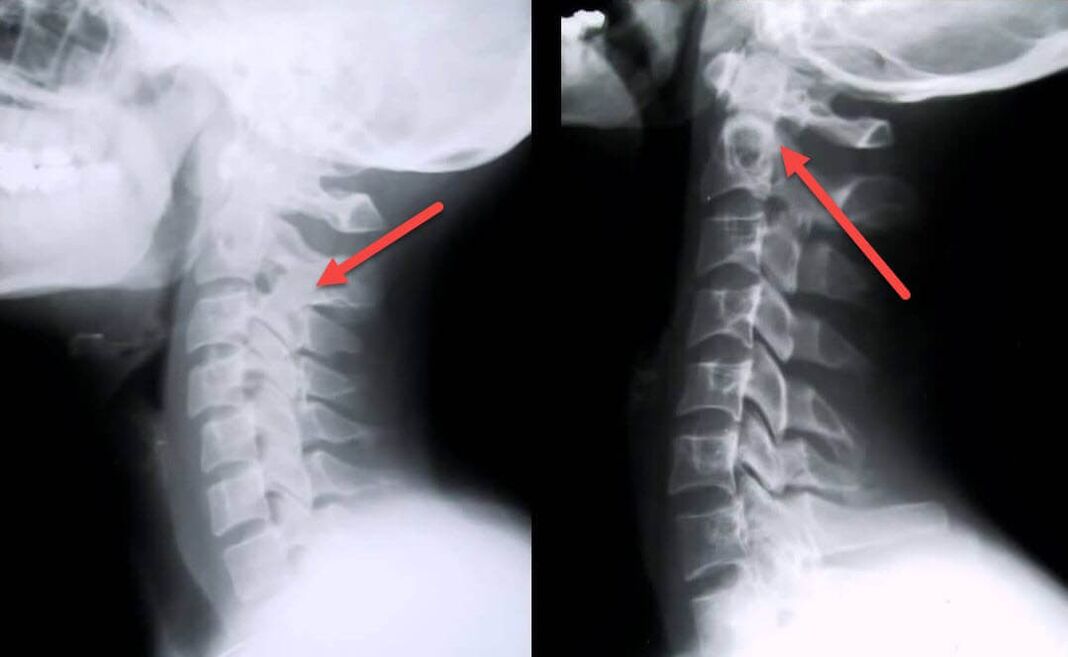

Najinformativnija dijagnostička metoda je radiografija. Patologije 1. stupnja odgovaraju 1. ili 2. radiološkom stadiju. Dobivene slike vizualiziraju tipične znakove bolesti.

| X-ray faze cervikalne osteohondroze 1. stupnja | Karakteristični znakovi |

|---|---|

| 1. faza | Manje promjene u zakrivljenosti kralježnice u cervikalnom području, koje zahvaćaju jedan ili više segmenata |

| Faza 2 | Lagano zadebljanje intervertebralnih diskova, deformacija uncinatnih nastavaka, ispravljanje lordoze, manje izrasline koštanih struktura. |